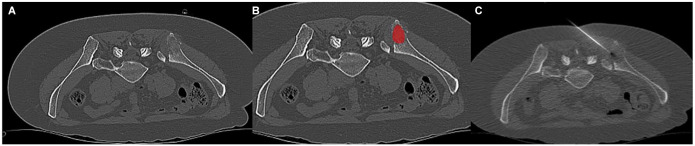

Methods: The present study included a total of 66 patients. All patients proceeded to undergo a CT-guided percutaneous bone biopsy, using an 11-gauge coaxial needle. Clinical and imaging characteristics as well as CT texture analysis were included in the analysis. Logistic regression analysis was performed to predict negative biopsy results.

Results: Overall, 33 patients had osteolytic metastases (50%) and 33 had osteoblastic metastases (50%). The overall positivity rate for the biopsy was 75%. The clinical model exhibited a predictive accuracy for a positive biopsy result, as indicated by an area under the curve (AUC) of 0.73 [95% confidence interval (CI) = 0.63-0.83]. Several CT texture features were different between Luminal A and Luminal B cancers; the best discrimination was reached for "WavEnHH_s-3" with a P-value of .002. When comparing triple-negative to non-triple-negative cancers, several CT texture features were different, the best discrimination achieved "S(5,5)SumVarnc" with a P-value of .01. For the Her 2 discrimination, only 3 parameters reached statistical significance, "S(4,-4)SumOfSqs" with a P-value of .01.